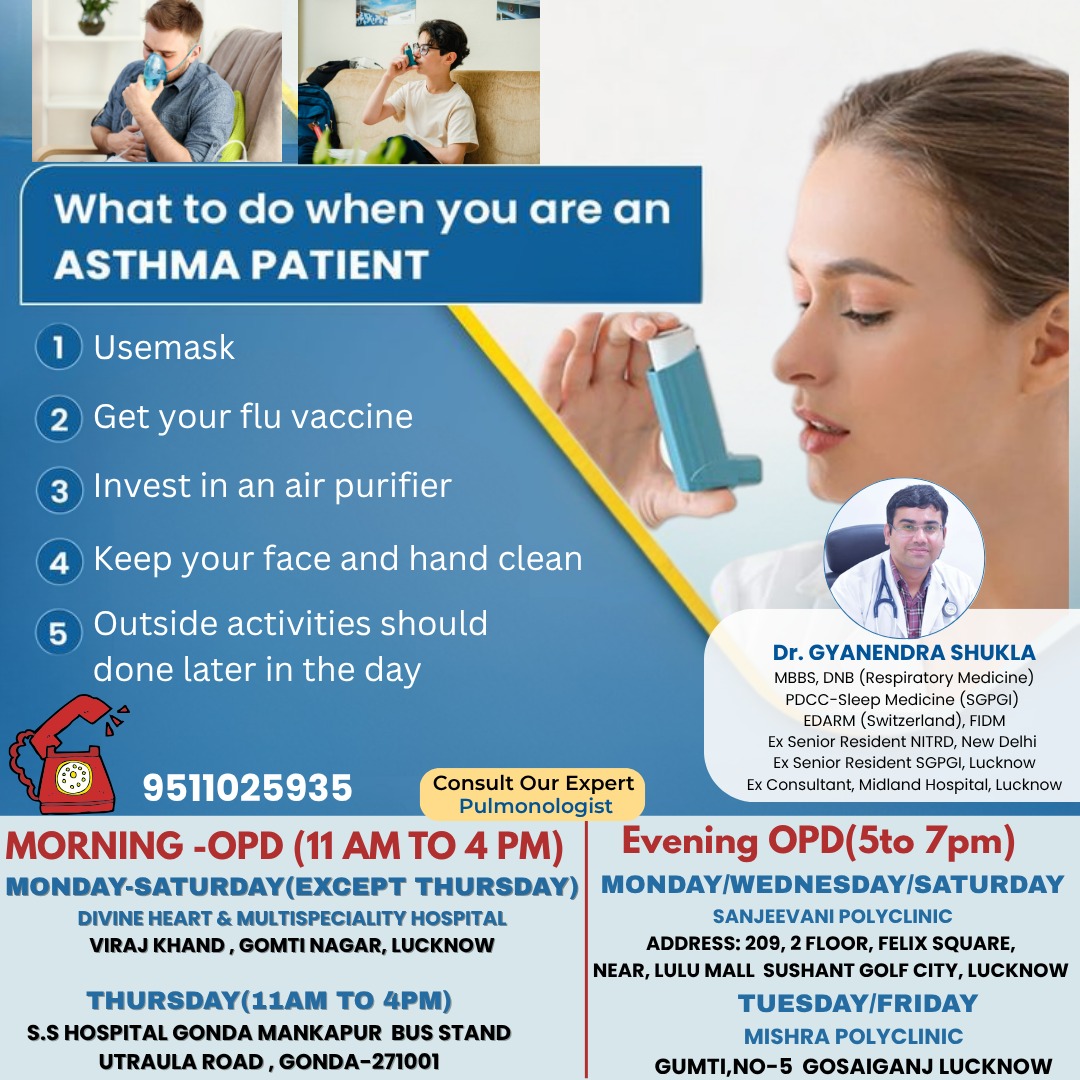

Dr. Gyanendra Shukla

M.B.B.S., DNB (Respiratory Medicine), PDCC-Sleep Medicine (SGPGI), EDARM (Switzerland), FIDM

Ex Senior Resident NITRD, New Delhi,

Ex Senior Resident SGPGI, Lucknow,

Ex Consultant, Midland Hospital, Lucknow.

Specialist in Tuberculosis, Asthma, COPD, ILD, Pneumonia, Allergy, Bronchoscopy, Chest Diseases, Critical Care, and Sleep Disorders.

Dr. Gyanendra Shukla is a distinguished medical professional with a stellar academic background and significant expertise in pulmonary medicine. He obtained his MBBS degree from the esteemed Madurai Medical College, followed by post-graduation in respiratory medicine from the prestigious National Institute of Tuberculosis and Respiratory Diseases in New Delhi.